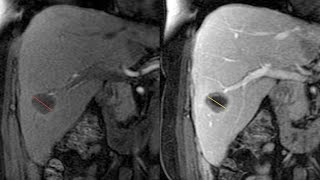

Система RECIST: как правильно оценить результат химиотерапии?

Обсудим с онкологами вопрос, как по лучевым исследованиям оценить эффективность химиотерапии злокачественных ...

Ильинская Больница